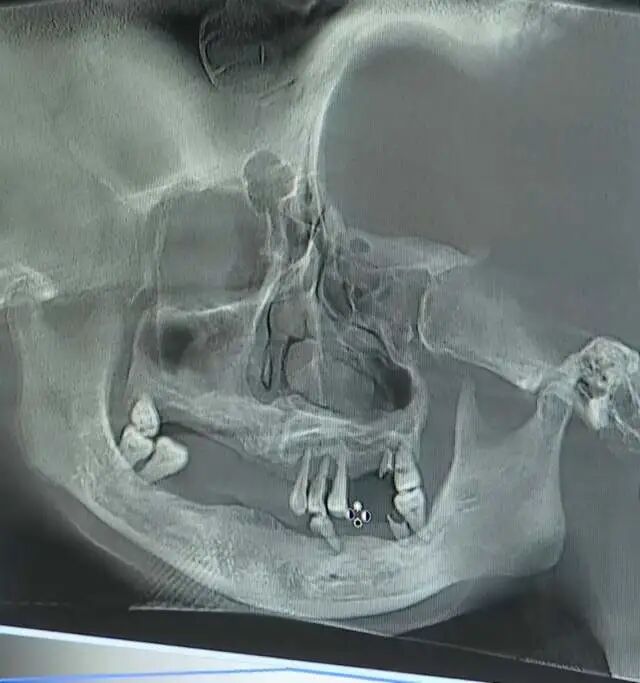

入院检查结果显示,杨某侠除精神及牙齿疾病外,未发现其他疾病。2月4日,徐州市口腔医学专家对杨某侠进行口腔检查和CBCT读片认为,杨某侠口腔卫生长期较差,患有牙周疾病,未进行治疗,部分牙齿逐步脱落。2月9日,经南京市口腔医院专家再次诊断,杨某侠患有重度慢性牙周炎,认为重度牙周炎可导致牙齿松动脱落。2月20日,省公安厅委托北京大学口腔医学院、首都医科大学北京口腔医院、浙江迪安鉴定科学研究院3名专家对杨某侠牙齿状况进行会诊,结论为杨某侠患有重度慢性牙周炎,未发现外伤致牙齿缺失的客观证据。

视频还公布了大家比较关注的杨某侠牙齿脱落的情况,从CT照片来看,她的牙齿只剩下寥寥几颗,官方结论为杨某侠患有重度慢性牙周炎,未发现外伤致牙齿缺失的客观证据。